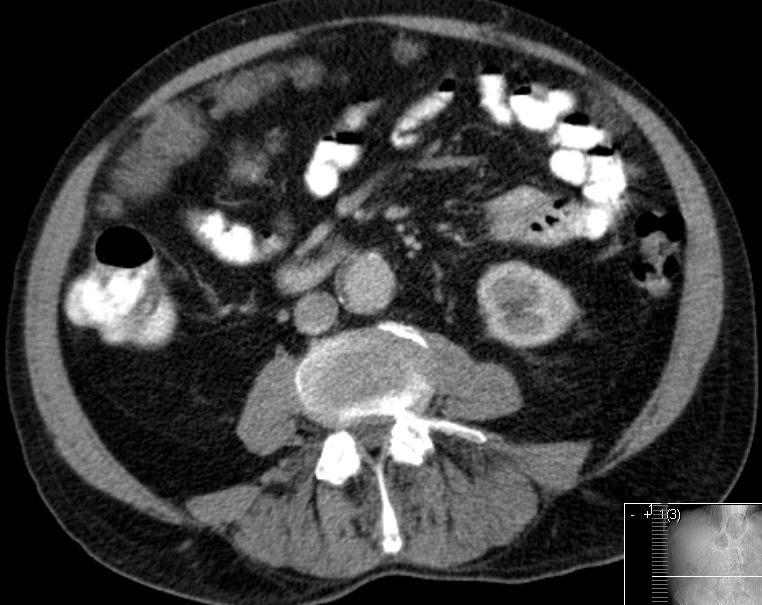

| Beispiele bildgebender Diagnostik von primären Colonkarzinomen | Zökum |

Colon ascendens |

Colon descendens | |

| CT-Lymphknoten-Staging | Ein praeoperatives CT kann den Lymphknotenstatus nicht zuverlässig bestimmen. | |||